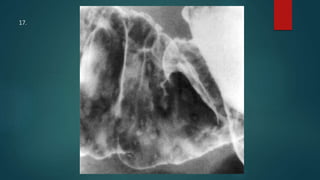

This document appears to be a medical report discussing several patients. It mentions a 35-year-old who was in a severe motor vehicle accident and an 81-year-old with a history of a non-vegetarian diet who had a perforated bowel from a chicken bone. The document provides few other details across its 25 numbered entries and was authored by Dr. Anish Choudhary for junior year 3 on May 30, 2016.